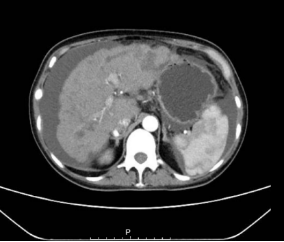

CT:1.左乳肿块,考虑乳腺癌,建议结合临床及专科检查; 2.肝内多发占位,考虑转移;3.胆囊结石;胆囊炎;4.右肺下叶短条灶。

image.png